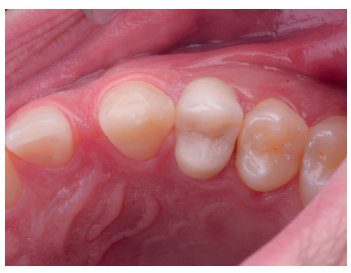

Una vez se hubo posicionado el diente 2 mm supragingival, se procedió a la ferulización con alambre de acero a los dientes adyacentes (Figuras 3 y 4) y la eliminación de cualquier tipo de oclusión, utilizando topes oclusales en los segundos molares inferiores. La ferulización se mantuvo durante dos semanas, coincidiendo con el momento de la endodoncia (Figura 5). El paciente fue citado para las revisiones periódicas y posteriormente para la rehabilitación del diente, una vez hubieron concurrido 6 semanas desde la extrusión, en las que se haya obtenido una cicatrización de los tejidos de soporte supracrestales10. En este momento, tras comprobar signos clínicos, periodontales y radiográficos saludables, se citó al paciente para el tallado y la confección mediante flujo digital (Cerec® System) de una endocorona de disilicato de litio (e.max®, Ivoclar Vivadent). El acondicionamiento de la corona se realizó con ácido fluorhídrico y silano, y para la cementación se utilizó cemento de resina (Calibra®, Dentsply Sirona).

Las revisiones se realizaron de forma periódica hasta los 12 meses de seguimiento (Figuras 6 y 7), observando en todas ellas signos clínicos saludables. El paciente no presentó reabsorción radicular, anquilosis, ni problema periodontal en los exámenes radiográficos que se realizaron desde el diagnóstico hasta el año (Figuras 8 -12); y la ganancia de ferrule obtenida de 2mm se mantuvo estable.

de seguimiento al año de la extrusión.

seguimiento al año de la extrusión.

momento de la rehabilitación.